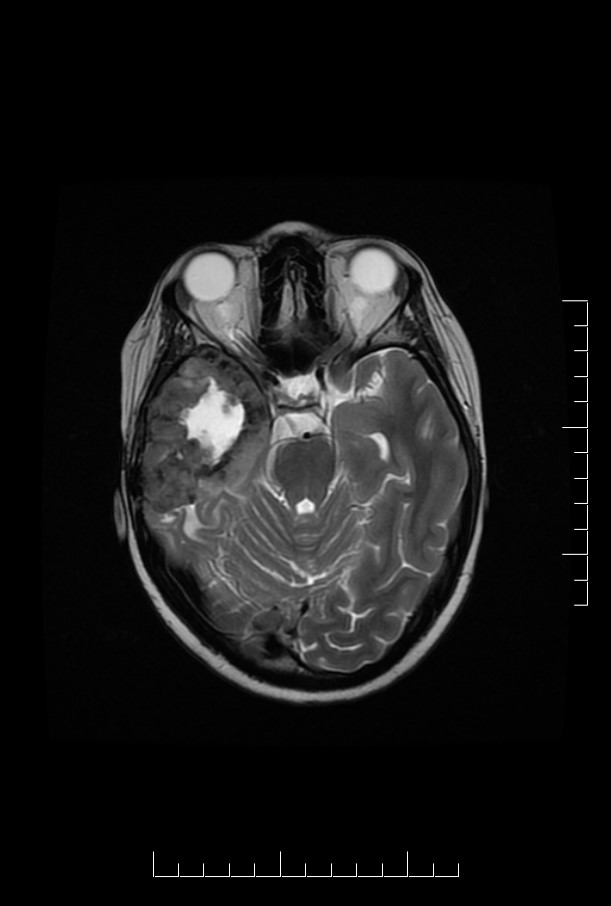

Case_4_T2.jpg